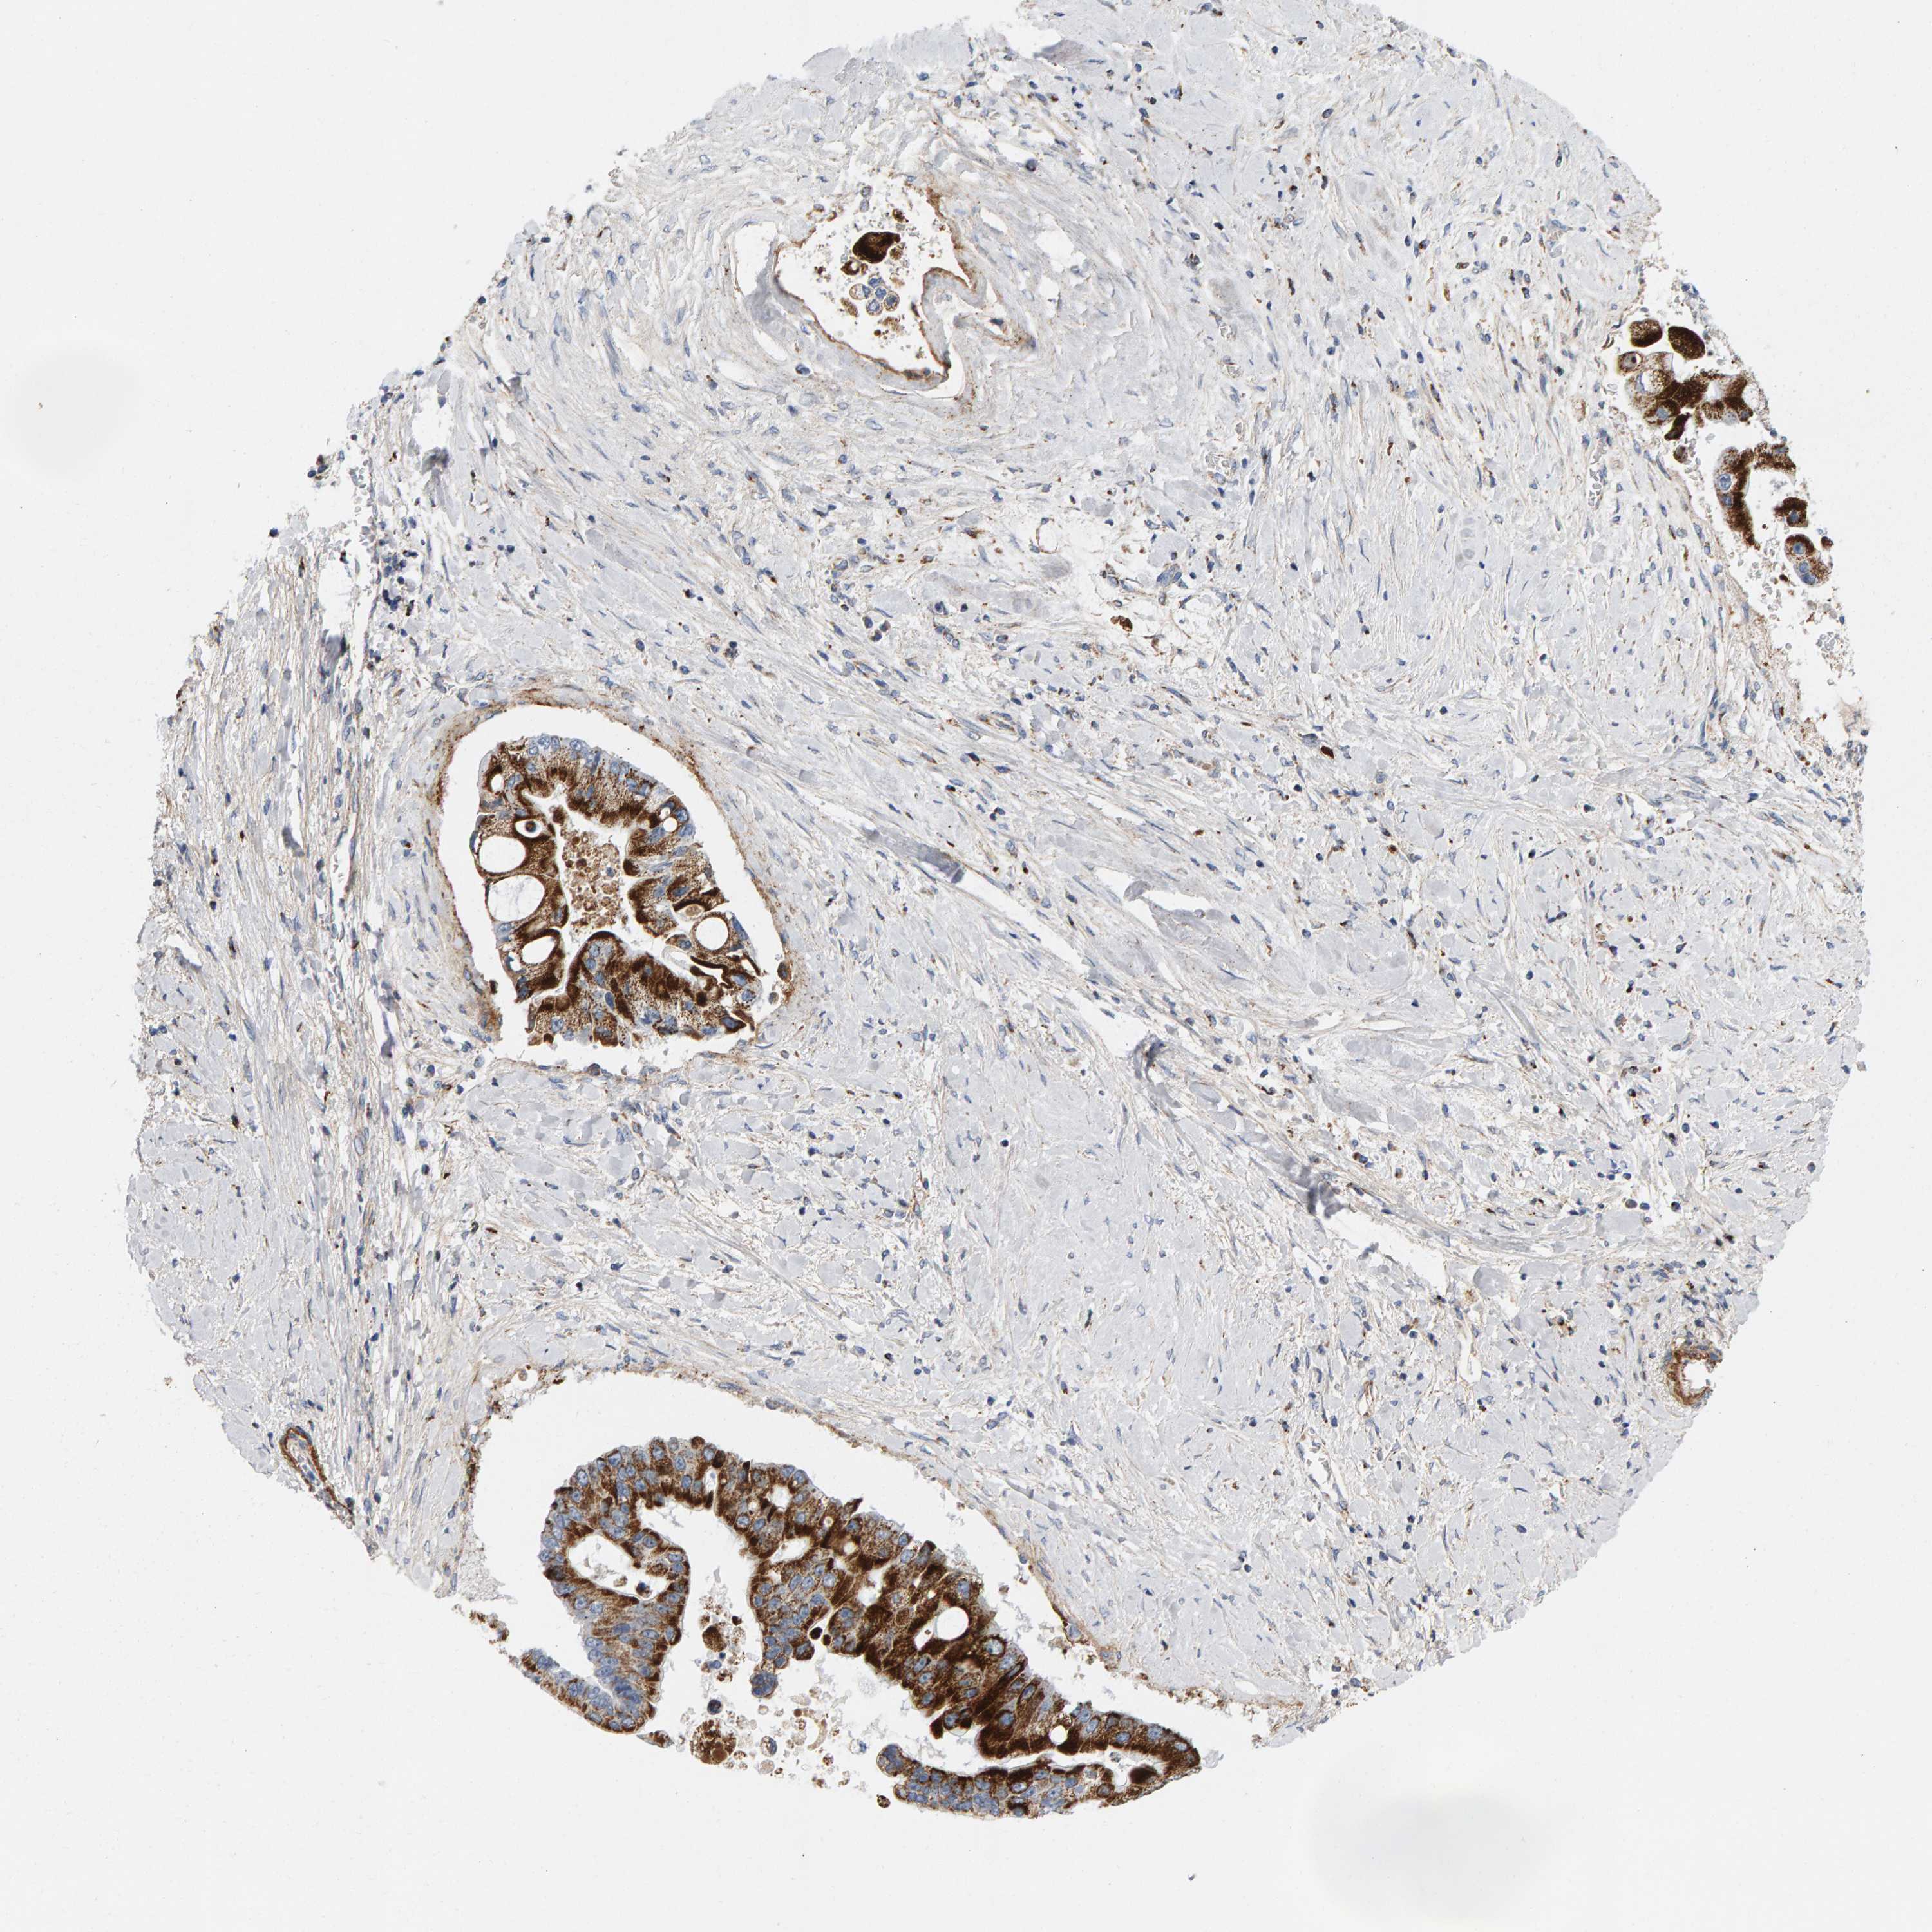

LIVER CANCER - Protein expressioni

A mouse-over function shows sample information and annotation data. Click on an image to view it in a full screen mode. Samples can be filtered based on level of antibody staining by selecting one or several of the following categories: high, medium, low and not detected. The assay and annotation is described here.

Note that samples used for immunohistochemistry by the Human Protein Atlas do not correspond to samples in the TCGA dataset.

Antibody stainingi

Antibody staining in the annotated cell types in the current human tissue is reported as not detected, low, medium, or high, based on conventional immunohistochemistry profiling in selected tissues. This score is based on the combination of the staining intensity and fraction of stained cells.

Each image is clickable and will lead to virtual microscopy that enables deeper exploration of all samples and also displays staining intensity scores, fraction scores and subcellular localization as well as patient and tissue information for each sample.

Antibody HPA023262

Staining

High

Medium

Low

Not detected

Intensity

Strong

Moderate

Weak

Negative

Quantity

>75%

75%-25%

<25%

None

Location

Nuclear

Cytoplasmic/membranous

Cytoplasmic/membranous,nuclear

Cholangiocarcinoma

Carcinoma, Hepatocellular, NOS